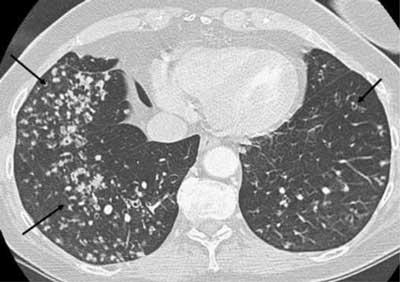

下图是我在肺部影像联盟看到的一个特殊空洞,支气管进入空洞,提示结核

上图所示,这是一个典型的肺结核的空洞(左图),可见不规则空洞与支

图10 粟粒性结核.65岁女性,患有肺炎,虽然治疗但未改善.